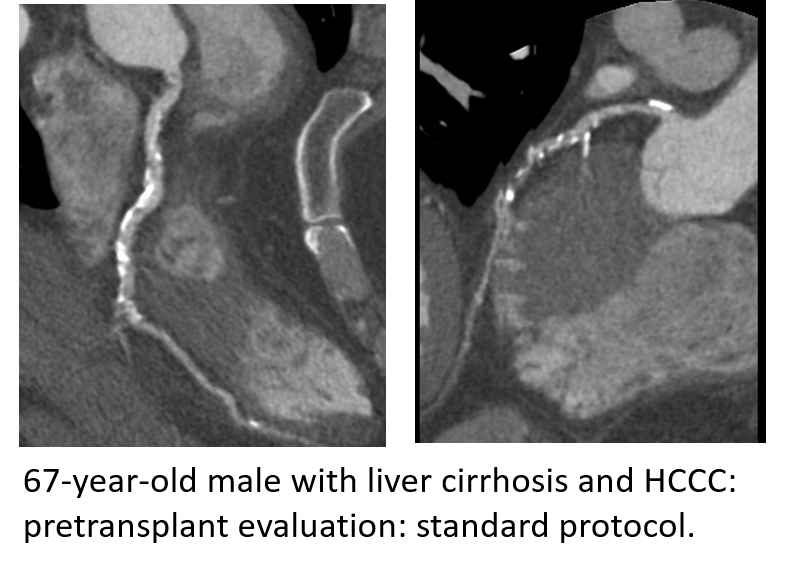

Pre-transplant liver and renal patients: The pre-transplant patients require coronary artery imaging to assess the risk of cardiac ischemia before major surgery such as the solid organ transplant. Unfortunately, standard coronary CTA imaging protocols yield suboptimal image quality in these patients due to their altered hemodynamic status. This results in either a suboptimal assessment of their pre-transplant risk or a need for invasive (and hence risky) imaging protocols such as coronary catheterization.

2. Pre-renal transplant patients suffer from decreased injection fraction and severe coronary calcifications. The major change that we implemented is the application of a bone algorithm to minimize the impact of artifacts caused by coronary calcifications.